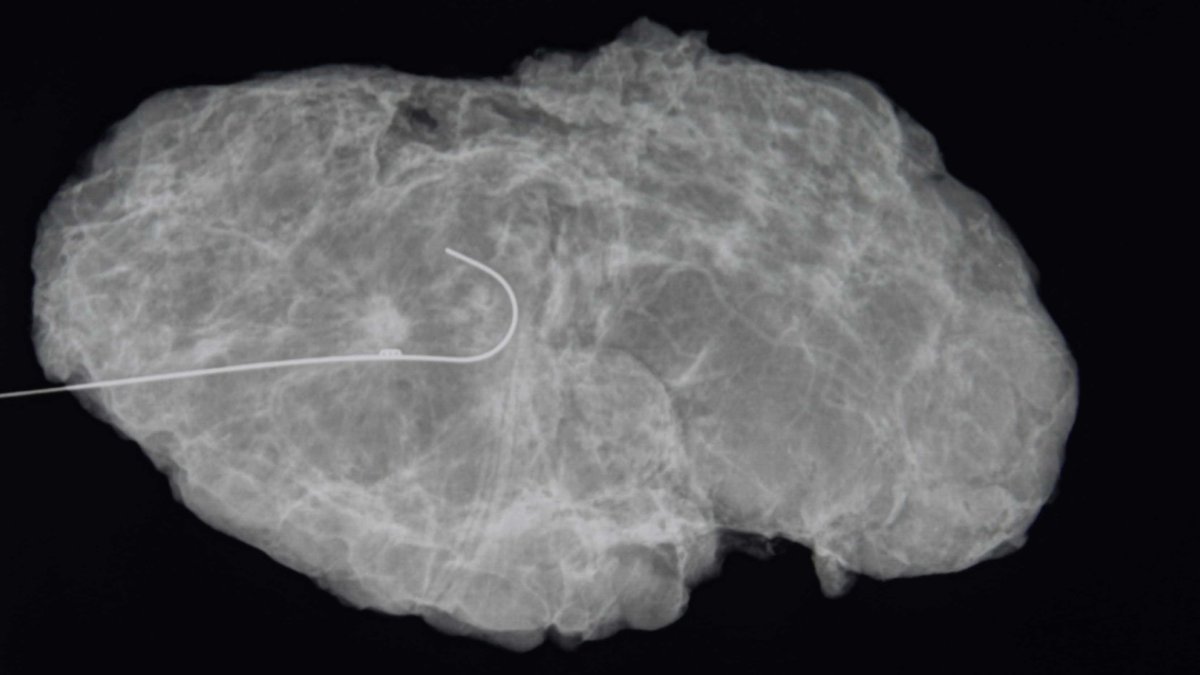

Ahora más pacientes de cáncer de mama pueden descartar la mastectomía y optar por esta cirugía

Muchas mujeres con dos o tres tumores de mama pueden arreglárselas con una lumpectomía en lugar de extirparse toda la mama, sugiere un nuevo estudio. En los últimos años, se han identificado más pacientes con tumores múltiples, como resultado de técnicas de imagen más sensibles que pueden revelar cánceres diminutos que alguna vez estuvieron ocultos.…